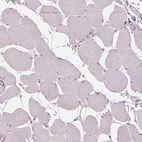

Immunohistochemical staining of human lymph node shows moderate positivity in non-germinal center cells.